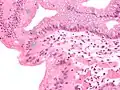

Células caliciformes (azul claro) no esôfago de Barrett

Células caliciformes (azul claro) no esôfago de Barrett